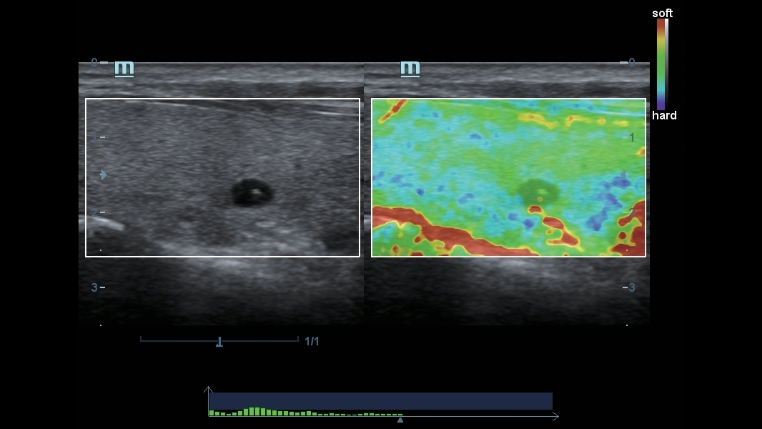

Teknologi pencitraan klasik: meningkatkan mutu diagnosis

Dengan penerapan teknologi pencitraan klasik, yang dimigrasikan dari sistem ultrasound yang sudah terbukti, DC-40 dengan Full HD memberikan peningkatan mutu akan detail gambar.

- iClear (teknologi pencitraan reduksi speckle)

- PSH (Pencitraan Phase Shift Harmonic)

- iBeam: Teknologi spatial-compounding imaging